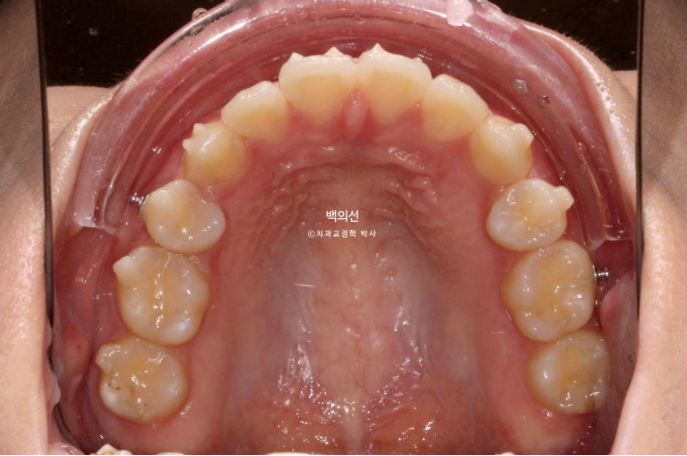

25.07

중심선은 정확히 맞으며

교합은 긴밀한 1급 교합관계가 보입니다.

남아있던 발치공간은 깔끔히 마무리 되었습니다.